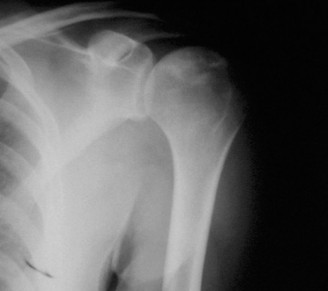

CASE 11 A 33-year-old male presents to the ED after a fall during a soccer game. He reports significant right shoulder pain and limited ROM. An x-ray taken in the ED is shown below (Fig. 2–29).

Figure 2–29

The correct answer is (A). The ED image shown in Figure 2–29 includes only an AP view of the right shoulder. In the setting of an acute injury and pain, technicians may be hesitant to obtain additional views. A single view, however, is insufficient to diagnose either a fracture, as orthogonal views are required, or a shoulder dislocation which is best seen on an axillary view (see Fig. 2–30). Answers B and C are inappropriate as a diagnosis has not been established yet and a dislocation or fracture must be conclusively ruled out. Answers D and E may be options that are exercised in the clinic but do not represent the next step in the management of this patient.